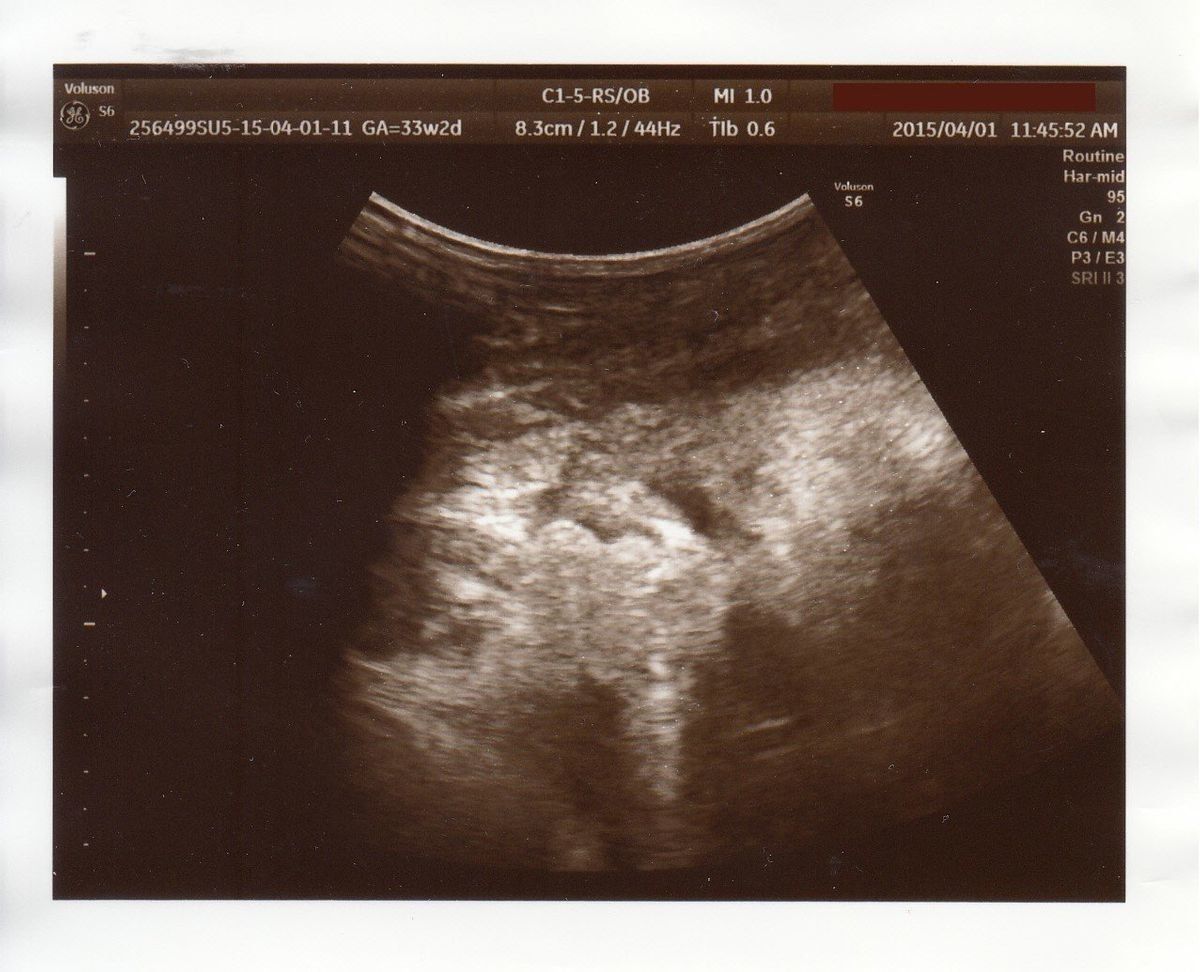

転院することに - 妊娠33週目のエコー写真

エコー写真は、ちょっとわかりにくいですが右側が頭、左側がお尻です。少しくびれたところが首、真ん中上下に腕が伸びています。左側、お尻の上下に足が見えます。赤ちゃんの推定体重は1735g。標準値を下回ってしまいました。何らかの原因で赤ちゃんの育ちが悪いと診断され、大きな病院への転院が決まります。とても動揺して、ネットで赤ちゃんの育ちが悪い原因を調べるなど、不安が消えない日々を過ごしました。

家から徒歩5分の産院から、車で1時間ほどの大学病院に転院することになりました。3ヶ所の大きな病院から選ぶように言われ、なんとなく車で行きやすそうなところに決めました。結婚で引っ越してきた土地なので、病院の情報や土地勘がありません。今思えば、一度持ち帰って、きちんと検討すればよかったと少し後悔しています。